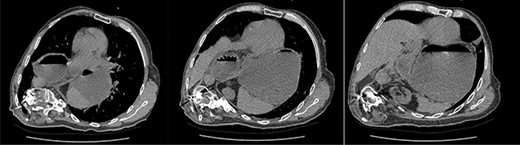

A 67-year-old man presented to the emergency department with sudden onset epigastric abdominal pain and vomiting, on a background of a known hiatus hernia awaiting surgical management. The patient continued passing flatus but was not able to tolerate any per oral fluid intake, vomiting any intake that was attempted. Medical history was relevant for severe KS, spina bifida, reflux, recurrent urinary tract infection, and an anterior approach spinal fusion surgery. Examination was significant for severe KS, with a soft and non-tender abdominal examination. Biochemically, the patient had a very mildly raised white cell count of 12.6 † 109/l. A CT of the abdomen and pelvis was obtained that identified the progression of a known hiatus hernia in comparison with an earlier CT, containing the distal portion of the stomach. The CT showed a distended and fluid filled oesophagus and stomach, along with fat stranding around the distal stomach, concerning for obstruction and possible strangulation of the moderate hiatus hernia, along with the known severe KS (see Figs 1 and 2). A nasogastric tube was placed to decompress the stomach (see Fig. 3). Following discussion with the patient regarding their current presentation and risks of operative management, laparoscopic hiatus hernia repair and fundoplication was undertaken, which was uncomplicated, although the dissection was difficult secondary to the severe scoliosis. Intra-operatively, it was noted that the hernial sac contained a grossly dilated stomach, with all hernial contents assessed as being viable, with nil signs of ischaemia. The peritoneal sac was not resected and left in situ, with a four-stitch horizontal posterior cruroplasty undertaken, along with a 180-degree anterior fundoplication. There was concern that recovery may be complicated by respiratory failure due to the severe KS; however, the patient had no respiratory compromise, begun passing flatus, opened his bowels, and tolerated a puree diet in the days following the operation. At post-operative clinic review 4 months following the hiatus hernia repair, the patient was well, described nil issues, and was tolerating a full diet.

Coronal slices of CT scan showing a moderate hiatus hernia with concern for obstruction and strangulation, with severe kyphoscoliosis.